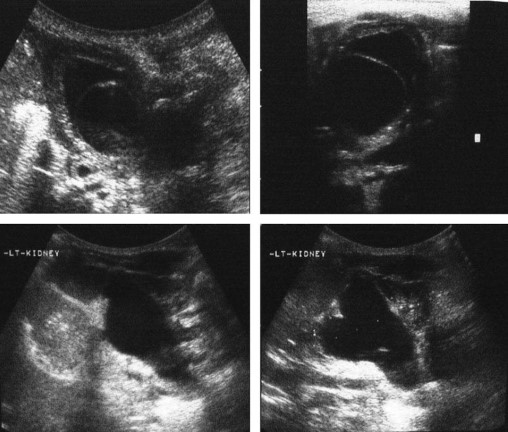

Interpretation of common urinalysis results: